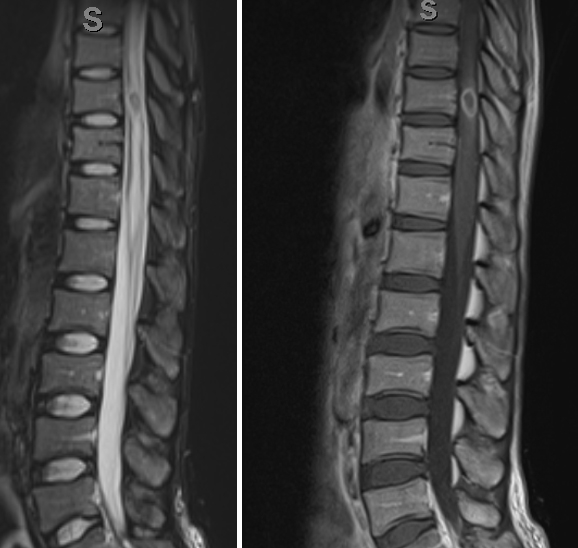

NMOSD MOG Ab Disease Sarcoidosis Paraneoplastic Dural AVF Cord Infarction Cervical Spondylosis